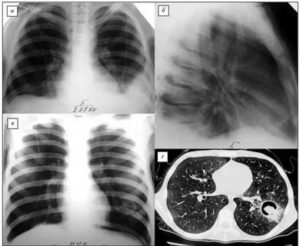

Важное значение в постановке диагноза имеет рентгенографическое обследование. На снимке патогены видны как округлые образования на поверхности легких. Взятие анализа мокроты больного позволяет определить вид грибкового возбудителя, что крайне важно для назначения будущего лечения.

Диагностические мероприятия, позволяющие выявить грибок в легкихМанипуляцияОписаниеРентгенологическое исследованиеПредоставляет возможность определить расположение очагов грибка в дыхательных органах.

Тем не менее, следует учитывать, что использование рентгенографии не считается эффективным диагностическим методом в случае грибкового поражения легочных тканей на ранних этапах течения патологии, так как имеется высокая вероятность диагностирования пневмонии хронического характера течения, опухоли, туберкулезной инфекции либо абсцесса. На поздних стадиях патологии при расшифровке рентген-снимка становятся заметными патологические изменения ребер, бронхиального древа и плевелы.

Применение компьютерных и визуальных методов в сочетании с анамнезом и клинической картиной позволяет поставить точный диагноз.

Чтобы исключить грибковый бронхит, проводят рентген, компьютерную томографию, бронхоскопию. Применение компьютерных и визуальных методов в сочетании с анамнезом и клинической картиной позволяет поставить точный диагноз.